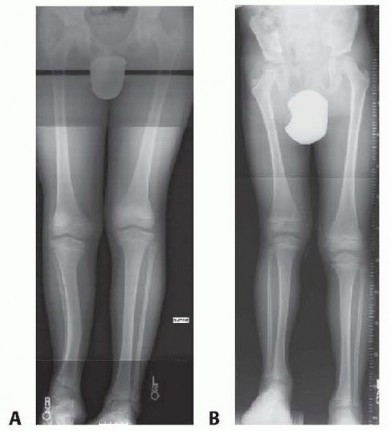

Guided Growth to Correct Limb Deformity DEFINITION The anatomic axis is the mid-diaphyseal line of a bone. Th…

Surgical Management of Blount Disease DEFINITION Blount disease, also known as idiopathic tibia vara and oste…